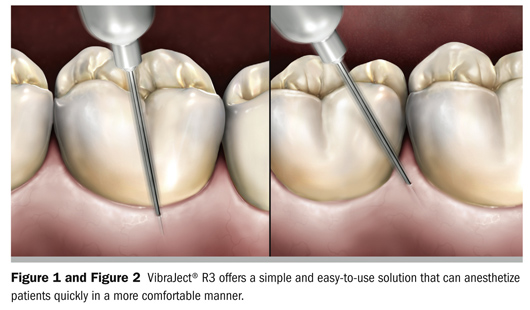

A vibrational device attached to a syringe uses this same concept of tricking the mind to recognize only the sensation caused by the “wiggle and jiggle” vibrations. The VibraJect® R3 (Miltex, Inc, York, PA) offers a simple and easy-to-use solution that can anesthetize patients quickly in a more comfortable manner (Figure 1 and Figure 2). Use of this two-piece device is simple: Just clip the VibraJect motor unit (a small battery-operated unit) onto the barrel of a conventional and/or intraligamentary syringe, turn it on, and use any standard technique for injecting the patient.